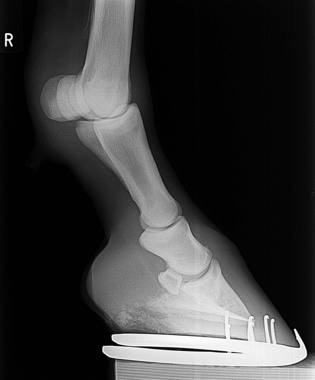

Die Klägerin war am 08.07.2010 mit ihrem Pferd beim beklagten Tierarzt vorstellig, nachdem sie an der Innenseite des rechten hinteren Beins eine Wunde entdeckt hatte. Der Beklagte versorgte die Verletzung und gab die Anweisung, das Pferd müsse zwei Tage geschont werden, könne aber dann wieder geritten werden, soweit keine Schwellung im Wundbereich eintrete. Am 11.07.2010 wurde das Pferd dann geritten, wobei der Klägerin Taktunreinheiten im Bereich des verletzten Beines auffielen. Das Reiten wurde daraufhin eingestellt. Am 14.07.2010 brach das Pferd sich beim Aufstehen das Bein. Eine Operation gelang nicht und das Pferd musste eingeschläfert werden.

Die Klägerin hat beantragt, den Beklagten zu verurteilen, an sie 114.146,41 Euro Schadensersatz sowie außergerichtliche Rechtsanwaltskosten zu zahlen. Sie begründete ihre Klage damit, dass die am 08.07.2010 behandelte Verletzung durch den Schlag einer Stute verursacht worden sei und dieser zu einer Fissur des darunterliegenden Knochens geführt habe. Innerhalb der nächsten Tage habe sich die Fissur zu der am 14.07.2010 diagnostizierten Fraktur entwickelt. Der Beklagte habe behandlungsfehlerhaft auf eine Lahmheits- und Röntgenuntersuchung des Pferdes verzichtet. Dabei hätte die Fissur erkannt werden können.